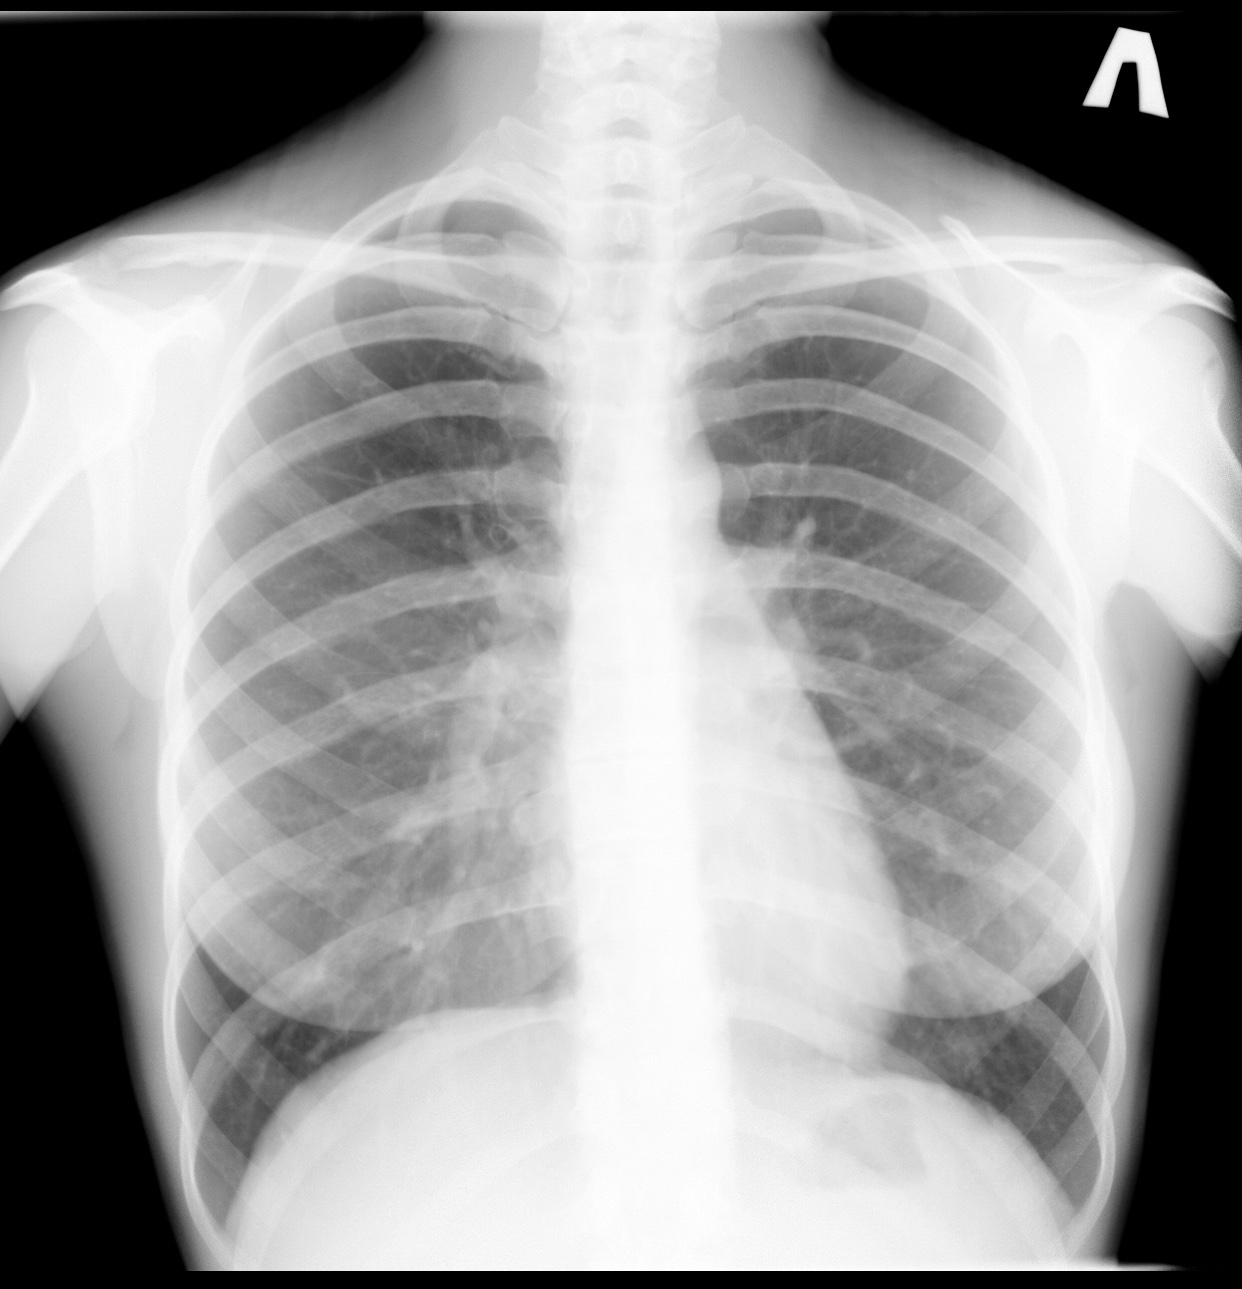

Снимок грудной клетки здорового ребенка: примеры и диагностика